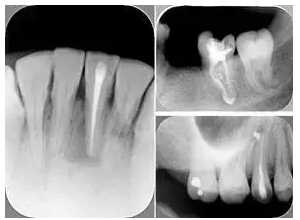

共有 4 張 X 線片,分別是術(shù)前、診斷絲 、主牙膠尖確認(rèn)、術(shù)后。

( 1 )術(shù)前:術(shù)前 X 線片用來了解牙齒的大概情況。術(shù)前預(yù)期為多根牙時 X 線片應(yīng)偏頭拍攝。

( 2 )診斷絲:根據(jù)術(shù)前 X 線片進(jìn)行開髓、根管的初步預(yù)備后,需要插入診斷絲,用來指示工作器械位置。常用 10 號或 15 號擴(kuò)大器作為診斷絲插入牙髓腔。

( 3 )主牙膠尖確認(rèn):通過術(shù)前預(yù)期和診斷絲診斷,明確工作長度、牙根走向,進(jìn)行根管預(yù)備。之后應(yīng)進(jìn)行主牙膠尖(中銼)確認(rèn),已明確根管是否適合充填。

( 4 )術(shù)后:觀察治療效果。

左圖為根管充填術(shù)后 X 線片。圖中可見,根管充填較好。右下圖有白色小點(diǎn),為側(cè)方加壓導(dǎo)致糊劑擠出所致,表明根管充填比較致密。

多根牙時候需進(jìn)行偏移投照,正位投照無法說明具體哪根牙根管充填效果。 二、根管預(yù)備及充填要求